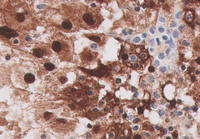

Figure 4-S100

The Rosai-Dorfman histiocytes are strongly positive for S100 with nuclear and cytoplasmic staining.  On higher power, emperipolesis with lymphocytes present in the cytoplasm of these histiocytes is apparent.  Emperipolesis is characteristic features in this disease.